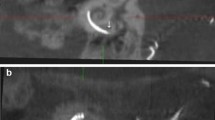

Postoperative imaging was performed using a DynaCT-equipped Axium Artis dTA angiography unit (Siemens Co., Erlangen, Germany) with a digital flat-panel detector [3, 7]. Two experienced head and neck surgeons and two head and neck radiologists independently analyzed the scans regarding scalar electrode position (ST versus SV insertion, intracochlear dislocation, angular insertion depth) and cochlear size (diameters in length and width) and used Impax 6 from Agfa Healthcare for reconstruction. The scans were not evaluated by the surgeons who, performed the CI surgery but by independent and experienced head and neck surgeons to reduce bias. All included electrode arrays were fully inserted. Cochlear size was evaluated in distance A from the round window to the lateral wall through the modiolus and perpendicular distance B [1, 2, 8]. The angular insertion depth was evaluated between the vectors of distance A and the distance through the bloom artefact of the apical electrode and the modiolus as described before [2, 8, 9]. Dislocation analysis and analysis of scalar position were performed on three-dimensionally reconstructed cross-sectional images as previously described [2, 8], i.e. the 3D-reconstruction could be rotated and browsed in whichever direction the specialists needed to come to their respective conclusion. Every image with discrepancy was reviewed and discussed interdisciplinary until a final agreement and measurement was achieved.

We compared preoperative HRCT scans to postoperative CBCT scans to examine the hypothesis that straight electrode arrays could lead to a mismatch of cochlear morphology measurements due to their more lateral electrode artifacts.

We excluded the hypothesis that the SSA could lead to larger cochlear measurements due to the lateral electrode array artifacts. Therefore, we compared preoperative HRCT scans to postoperative CBCT scans. We evaluated both scans blinded and independently and did not find different measurements for either distance A or B.